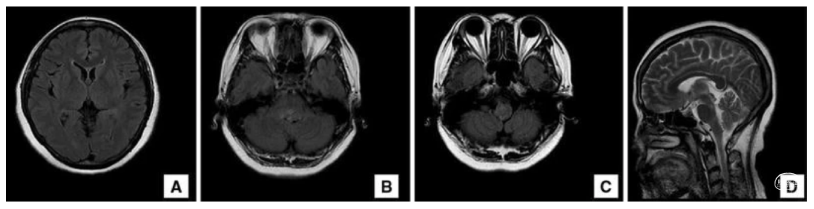

影像学看着像典型的“延髓背外侧综合征”

CSF electrophoresis demonstrated oligoclonal bands with a high IgG index. AQP4-Ab was positive (1:10) both in blood and CSF. Thoracic spine MRI studies did not reveal any abnormality. A diagnosis of neuromyelitis optica spectrum disorder was made based on Wingerchuk’s criteria (myelitis associated with brain lesions typical of neuromyelitis optica).

脑脊液电泳显示寡克隆条带并IgG指数增高的。AQP4-抗体在血和脑脊液中均呈阳性(1:10)。胸椎MRI检查未发现任何异常。按照Wingerchuk标准明确诊断为视神经脊髓炎谱系障碍(脊髓炎合并典型的视神经脊髓炎脑部病变)。开始静脉滴注甲基强的松龙1g/d,5d后转为口服。然后加硫唑嘌呤。治疗3天后逐渐恢复,20天后可自主行走。

Cerebral MRI performed 7 months later did not show any new lesions, and the dorsolateral medullary lesion had significantly reduced in size. She has not experienced any clinical relapses during the follow-up period.

7个月后进行的脑部MRI检查没有发现任何新的病灶,而且髓质背外侧病灶的大小明显缩小。在随访期间,她没有出现任何临床复发。